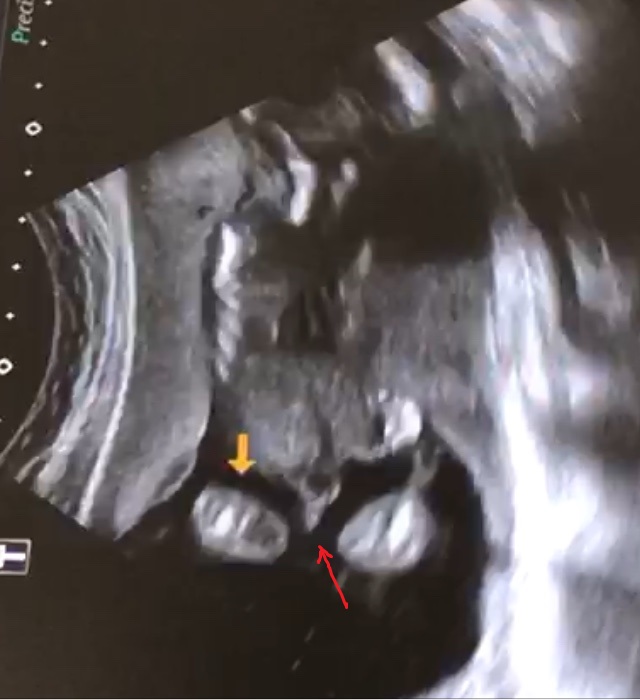

А теперь после маминого задумчивого: "мальчик...ну что же с ними, этими мальчишками, делать..? я даже себе пока не представляю.", пересмотрела видео с УЗИ и решила задать вопрос опытным мамам. Срок на картинке 17 недель.

То, на что указывает красная стрелочка- это не обман зрения?😜